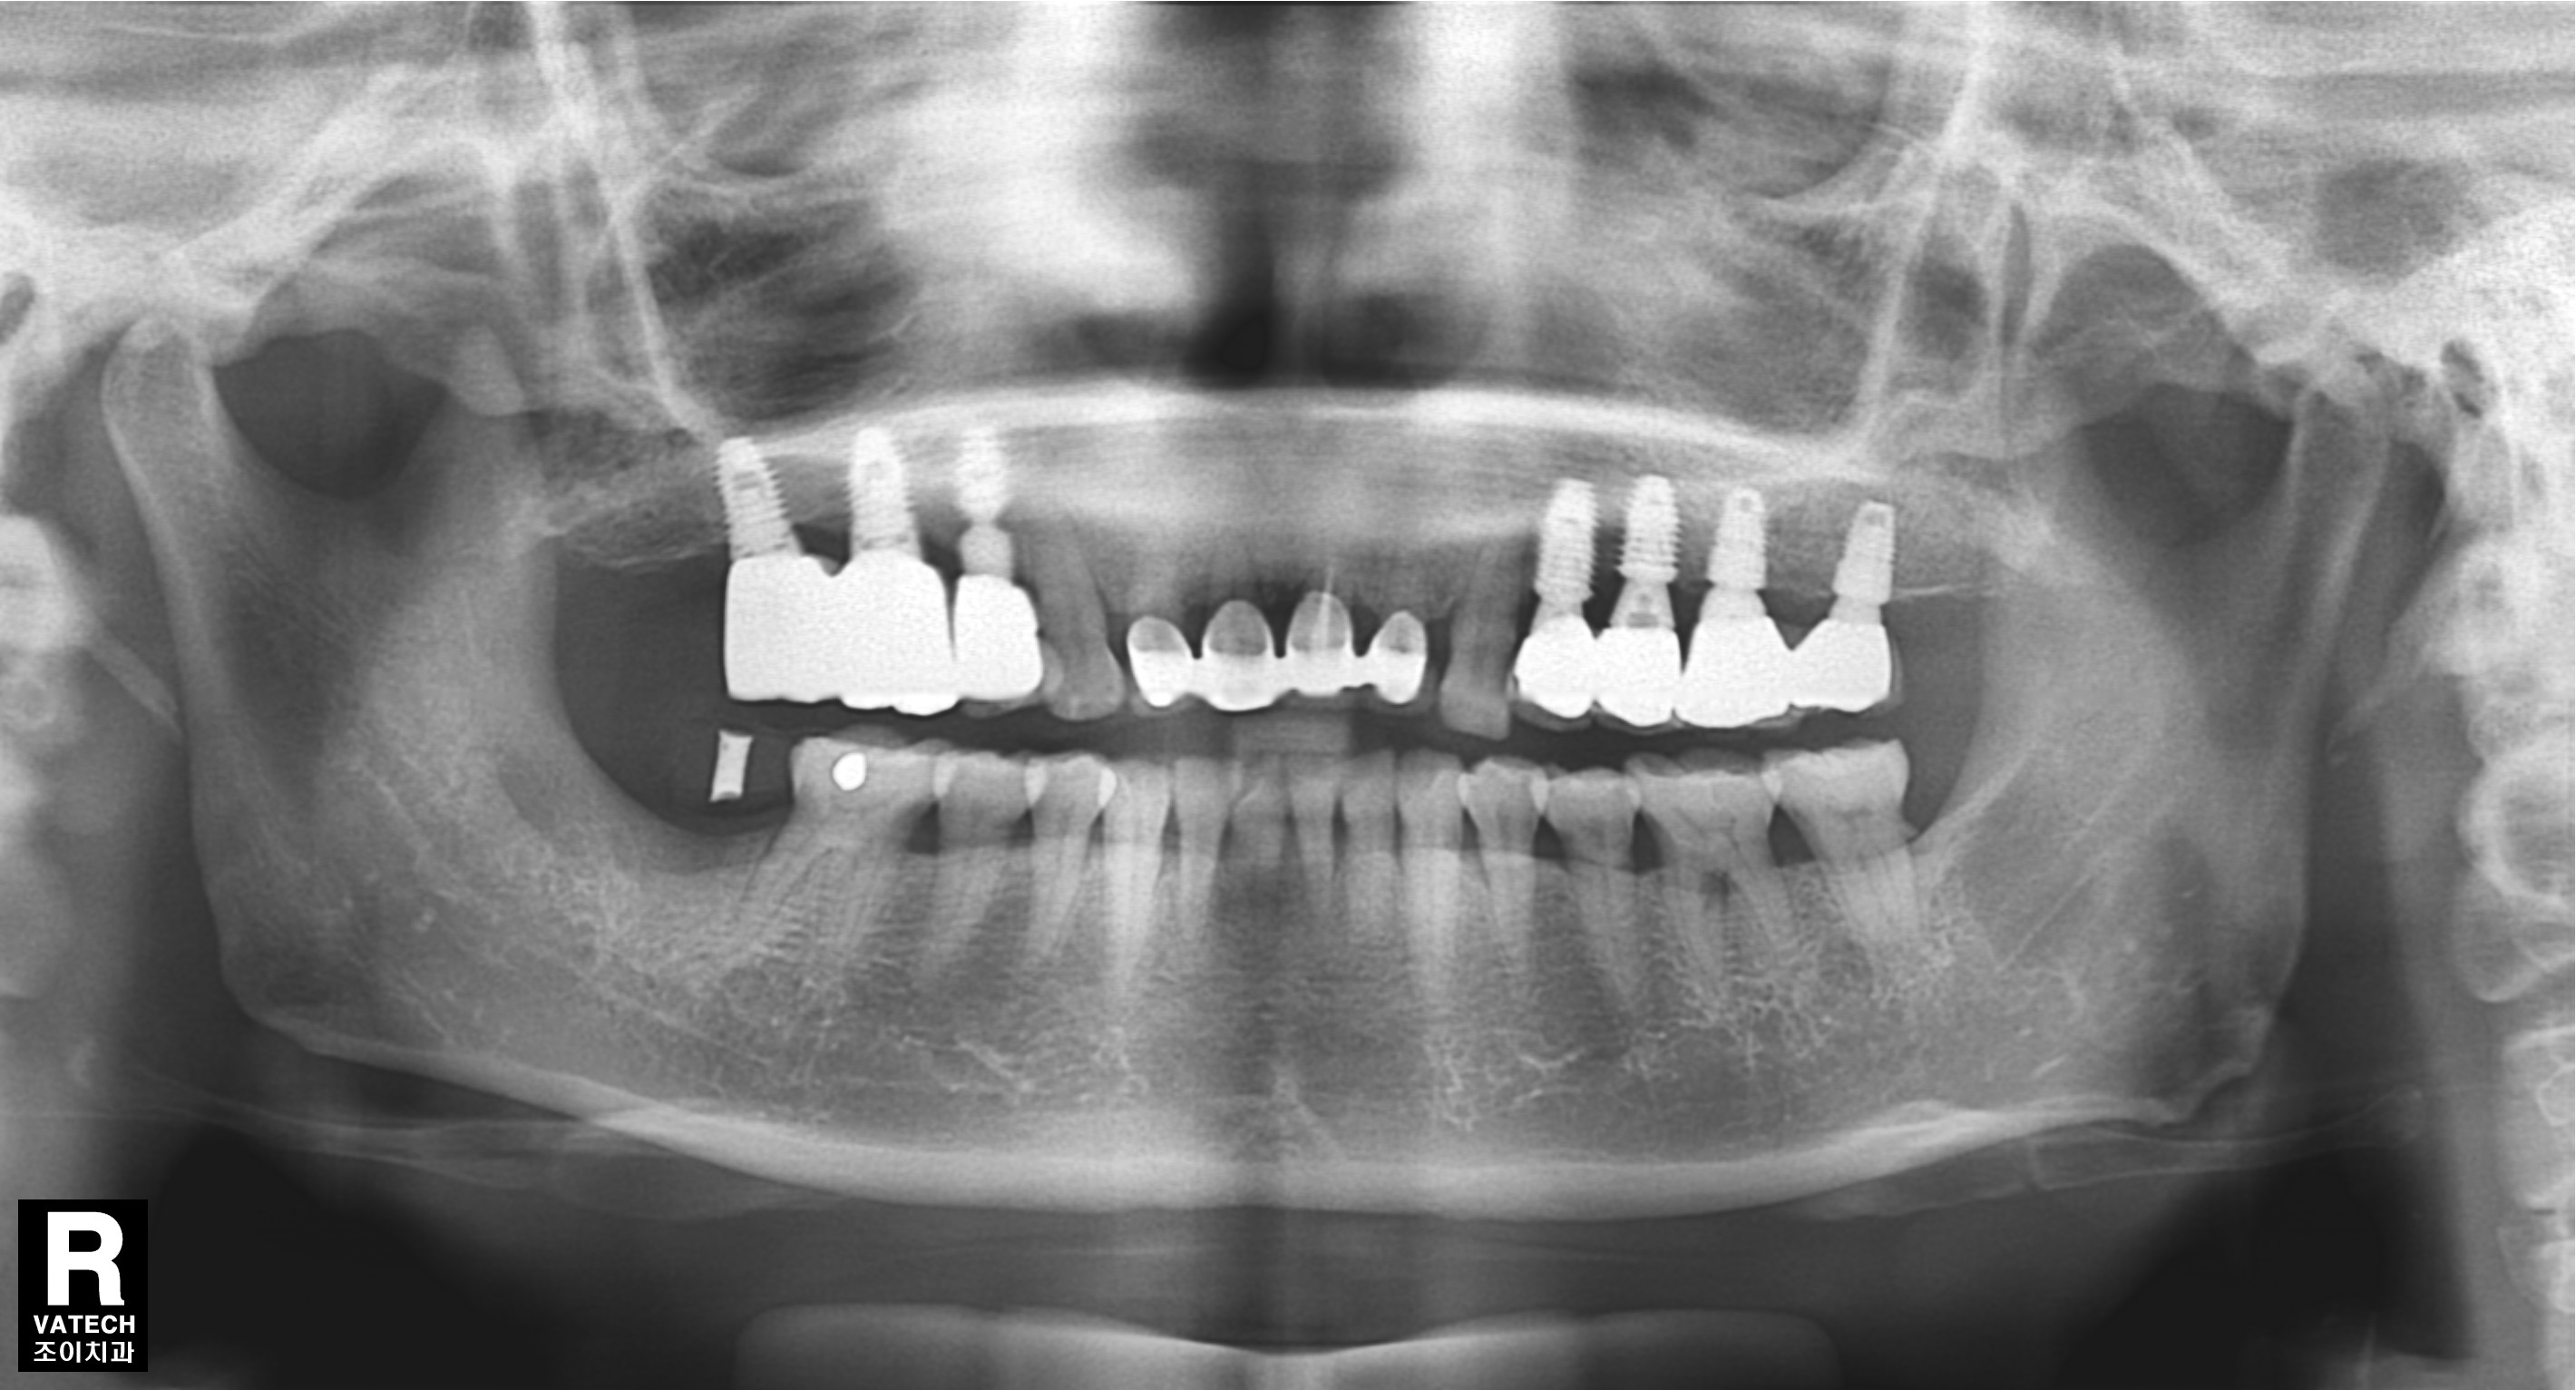

#15.16 부위로 타병원에서 수차례 실패했던 임플란트의 치료사례입니다.

임플란트 제거, 염증제거,티탄메쉬 골이식(bone graft), 서두르지 않고 충분한 경과관찰.